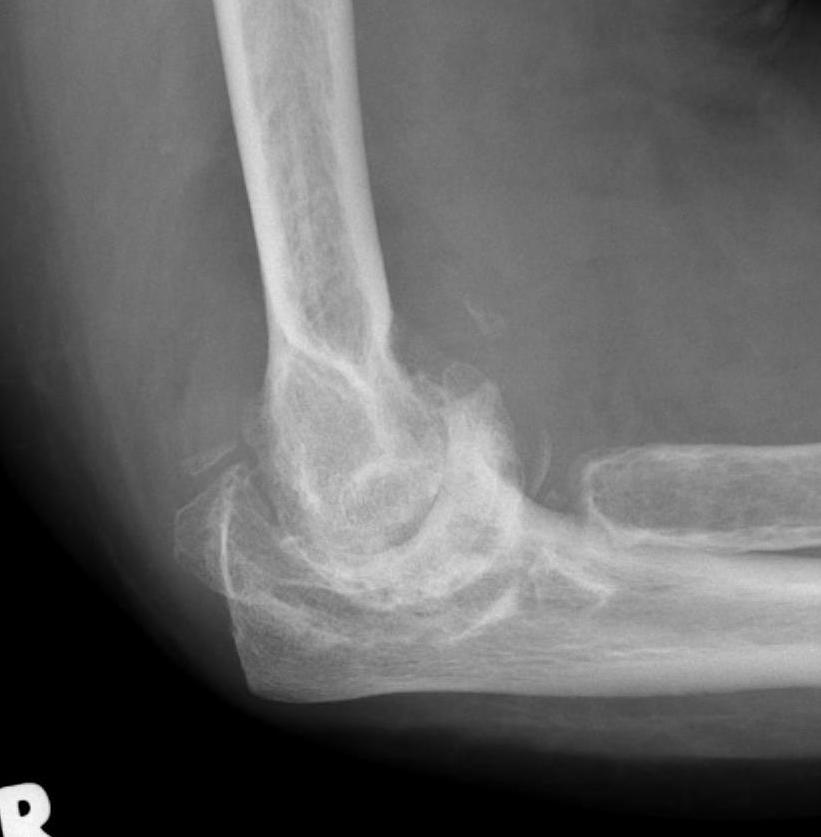

Xray

Articular destruction/ cysts / osteopenia /structural bone loss